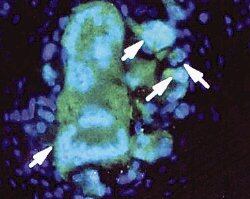

Allí inician una 'comunicación' con las células sinoviales, las células que recubren las articulaciones. En el proceso de ese diálogo entre células se liberan proteínas (entre ellas la interleucina 1) que hacen que se active la inflamación.

Los científicos buscaron una forma de bloquear a la interleucina 1. El gen que libera la proteína antagonista de la interleucina 1 fue la respuesta correcta, pues inhibe la acción de dicha proteína.

El ensayo clínico se diseñó para comprobar la seguridad de la terapia. Por ello, en el proceso se hizo la introducción del gen en células que habían sido extraídas del cuerpo, cultivadas en el laboratorio y luego analizadas, antes de ser introducidas en las articulaciones de las nueve pacientes.